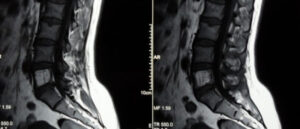

Гемангиома позвоночника

Если во время исследования у человека была выявлена гемангиома позвонка, не стоит впадать в панику и бояться, что это опасное заболевание. В большинстве случаев опухоль считается доброкачественной, и если она не вызывает болей и дискомфорта, никакого лечение не требуется. Но бывают случаи, когда происходит все наоборот, тогда стоит обратиться к врачу, который назначит лечение. Рассмотрим, …